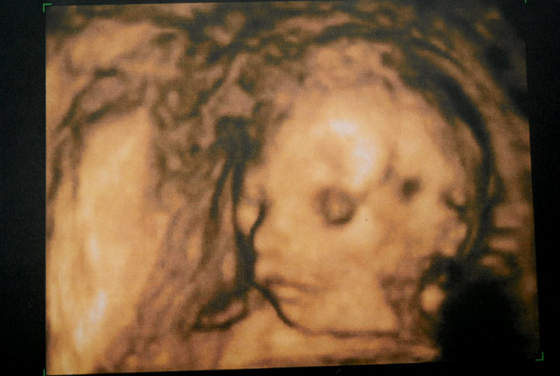

A to moja Lilianna. :) Na wizycie wszystko ok, połówkowe bez zastrzeżeń. Oczywiści wyszło o prawie 2 tygodnie mniejsze niż wg OM,czyli poślizg nadal zaliczamy. (wg OM to 21t6d a wg USG uśredniona wartość to 20t0d), termin wg tego usg wyszedł na 12 sierpnia (wg tego w 12 tygodniu 10 sierpnia także przyzwyczajam się do myśli,że to jednak nastąpi później).

Lilunia mocno sie nie ruszała,tak jak myślałam- leniuszek. Jstem spokojniejsza.Aaaa wagi nie znam , wymiar ciemieniowo-siedzeniowy to 14,6cm więc do wielkoludów nie należy ale wg kości udowej ma długie nóżki ;) także pewnie to się jakoś wyrównuje.